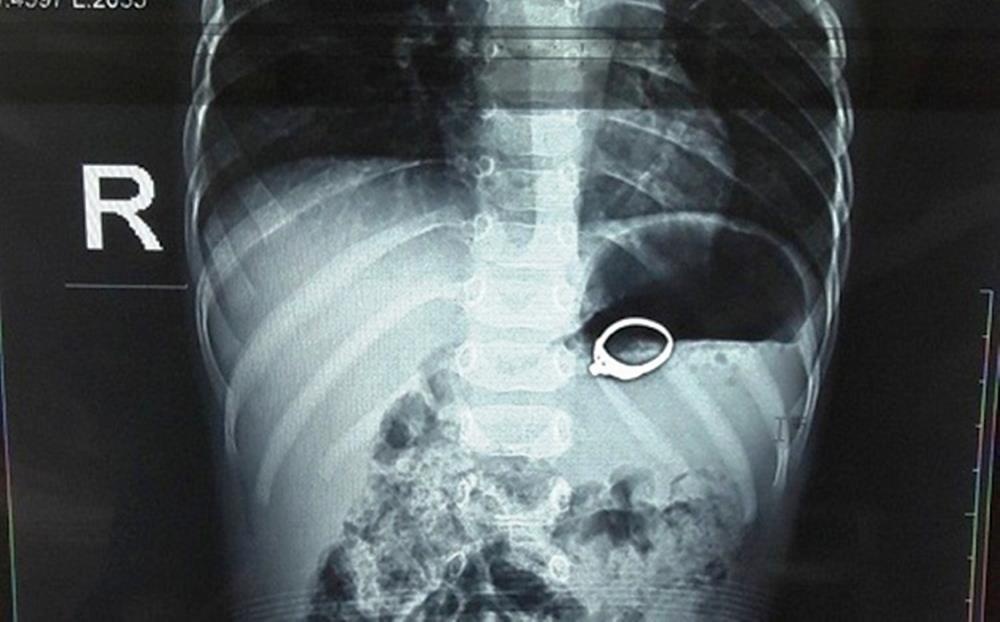

| Chiếc nhẫn trong dạ dày của cháu Đ. Ảnh: Bệnh viện cung cấp. |

Các bác sĩ cho biết chiếc nhẫn có đính đá. Dưới sự tác động của co bóp dạ dày, nó gây xước niêm mạc, xung huyết dạ dày của người bệnh.